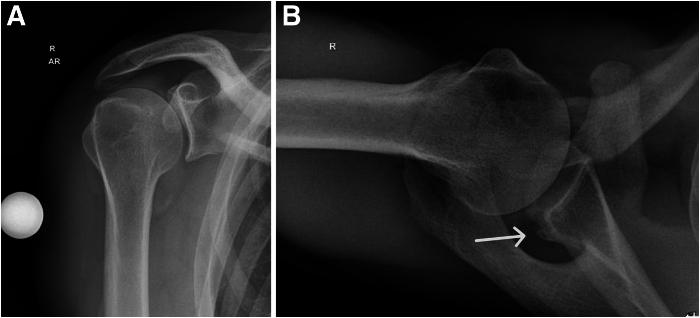

使用同侧肩胛冈的三层皮质自体骨移植进行关节镜下后骨块稳定术。

Arthroscopic Posterior Bone Block Stabilization Using a Tricortical Autograft of the Ipsilateral Scapular Spine.

Posterior bone grafting represents an emerging therapeutic approach for addressing recurrent instability in the posterior shoulder, particularly when coupled with substantial glenoid bone loss. Although not as prevalent as anterior instability, recent years have witnessed the development of numerous open and arthroscopic bony reconstruction methods. A technical gold standard for posterior bone grafting remains undefined, leading to ongoing advancements in bone grafting techniques. In response to past challenges associated with screw fixation, metal-free arthroscopic fixation procedures have been introduced to the realm of bone grafting. These metal-free methods often entail intricate transglenoid drilling, which poses potential surgical complexities and risks to both posterior and anterior soft tissues, as well as neurovascular structures. Therefore, we introduce an arthroscopic approach to posterior bone grafting using PEEK (polyether ether ketone) anchors with interconnected sutures and a scapular spine autograft. This method overcomes previous hurdles by facilitating the restoration of the posterior glenoid bone stock with precise positioning and secure fixation of the tricortical scapular spine bone autograft.

摘要